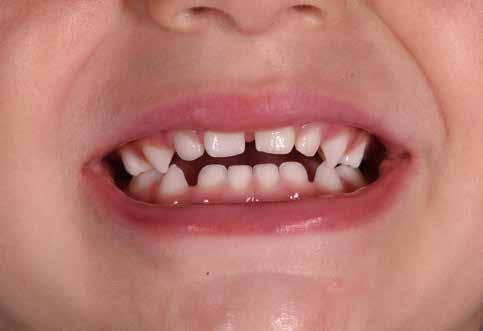

Figg. 58-61 > Open-bite da abitudine viziata: succhiamento protratto del dito in una bimba di sei anni.

62-68 > Open-bite da abitudine viziata: succhiamento protratto del dito in una bimba di sette anni. Notare bene come il succhiamento protratto del dito determini la spinta indietro della mandibola, l’iposviluppo trasversale del mascellare superiore e, quindi, il conseguente open-bite grave, spesso aggravato anche dall’aumento della divergenza facciale.